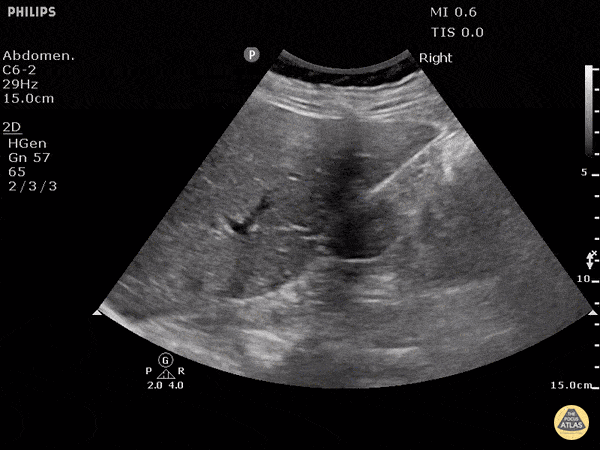

No free fluid in Morison's pouch. Dr. Justin Bowra

https://www.thepocusatlas.com/trauma